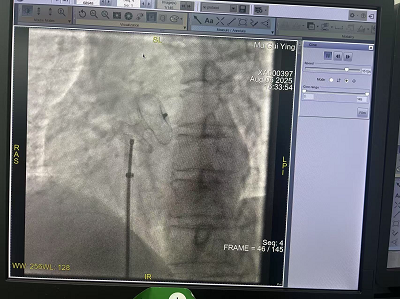

患者母某某,女,58岁。因反复出现心悸、头痛症状5年多。2025年7月25日,于我院内科二病区(心内科)求治,结合辅助检查,科内会诊,明确诊断为房间隔缺损(继发孔型),为其制定房间隔缺损(ASD)介入封堵术进行治疗。

住院期间,我院心内科专家团队王思俊(副院长)、宇何健(内科二病区主任)、赵子凡(主任医师)在广元市第一人民医院心内科陈玺全主任指导下成功开展广元市县(区)域首例房间隔缺损(ASD)介入封堵术,标志着本地区先天性心脏病治疗迈入微创介入新时代。患者术后恢复良好,次日即可下床活动,3天后康复出院。

2.安全性高:全程在超声及X线引导下完成,精准定位,出血量不足10ml,显著降低感染风险。